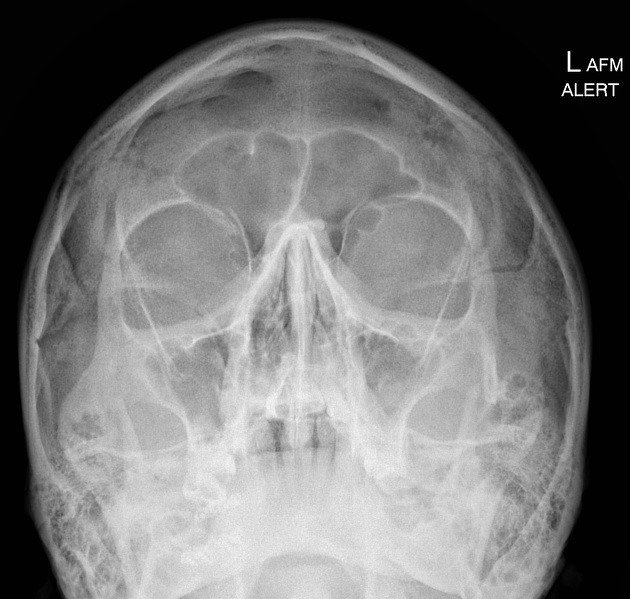

Contemporary zygomatic implant protocol development requires systematic evaluation of complex anatomical relationships through advanced imaging techniques. Optimal CBCT protocols employ slice thickness of 0.2-0.3mm for detailed reconstruction, with extended field of view encompassing the complete zygomatic arch. Density-based segmentation enables accurate boundary delineation essential for precise surgical techniques planning.

Systematic evaluation encompasses residual alveolar ridge morphology and bone quality assessment, maxillary sinus dimensions with detailed septation analysis, zygomatic bone volume evaluation with optimal trajectory corridor identification, and comprehensive neurovascular structure relationship mapping.